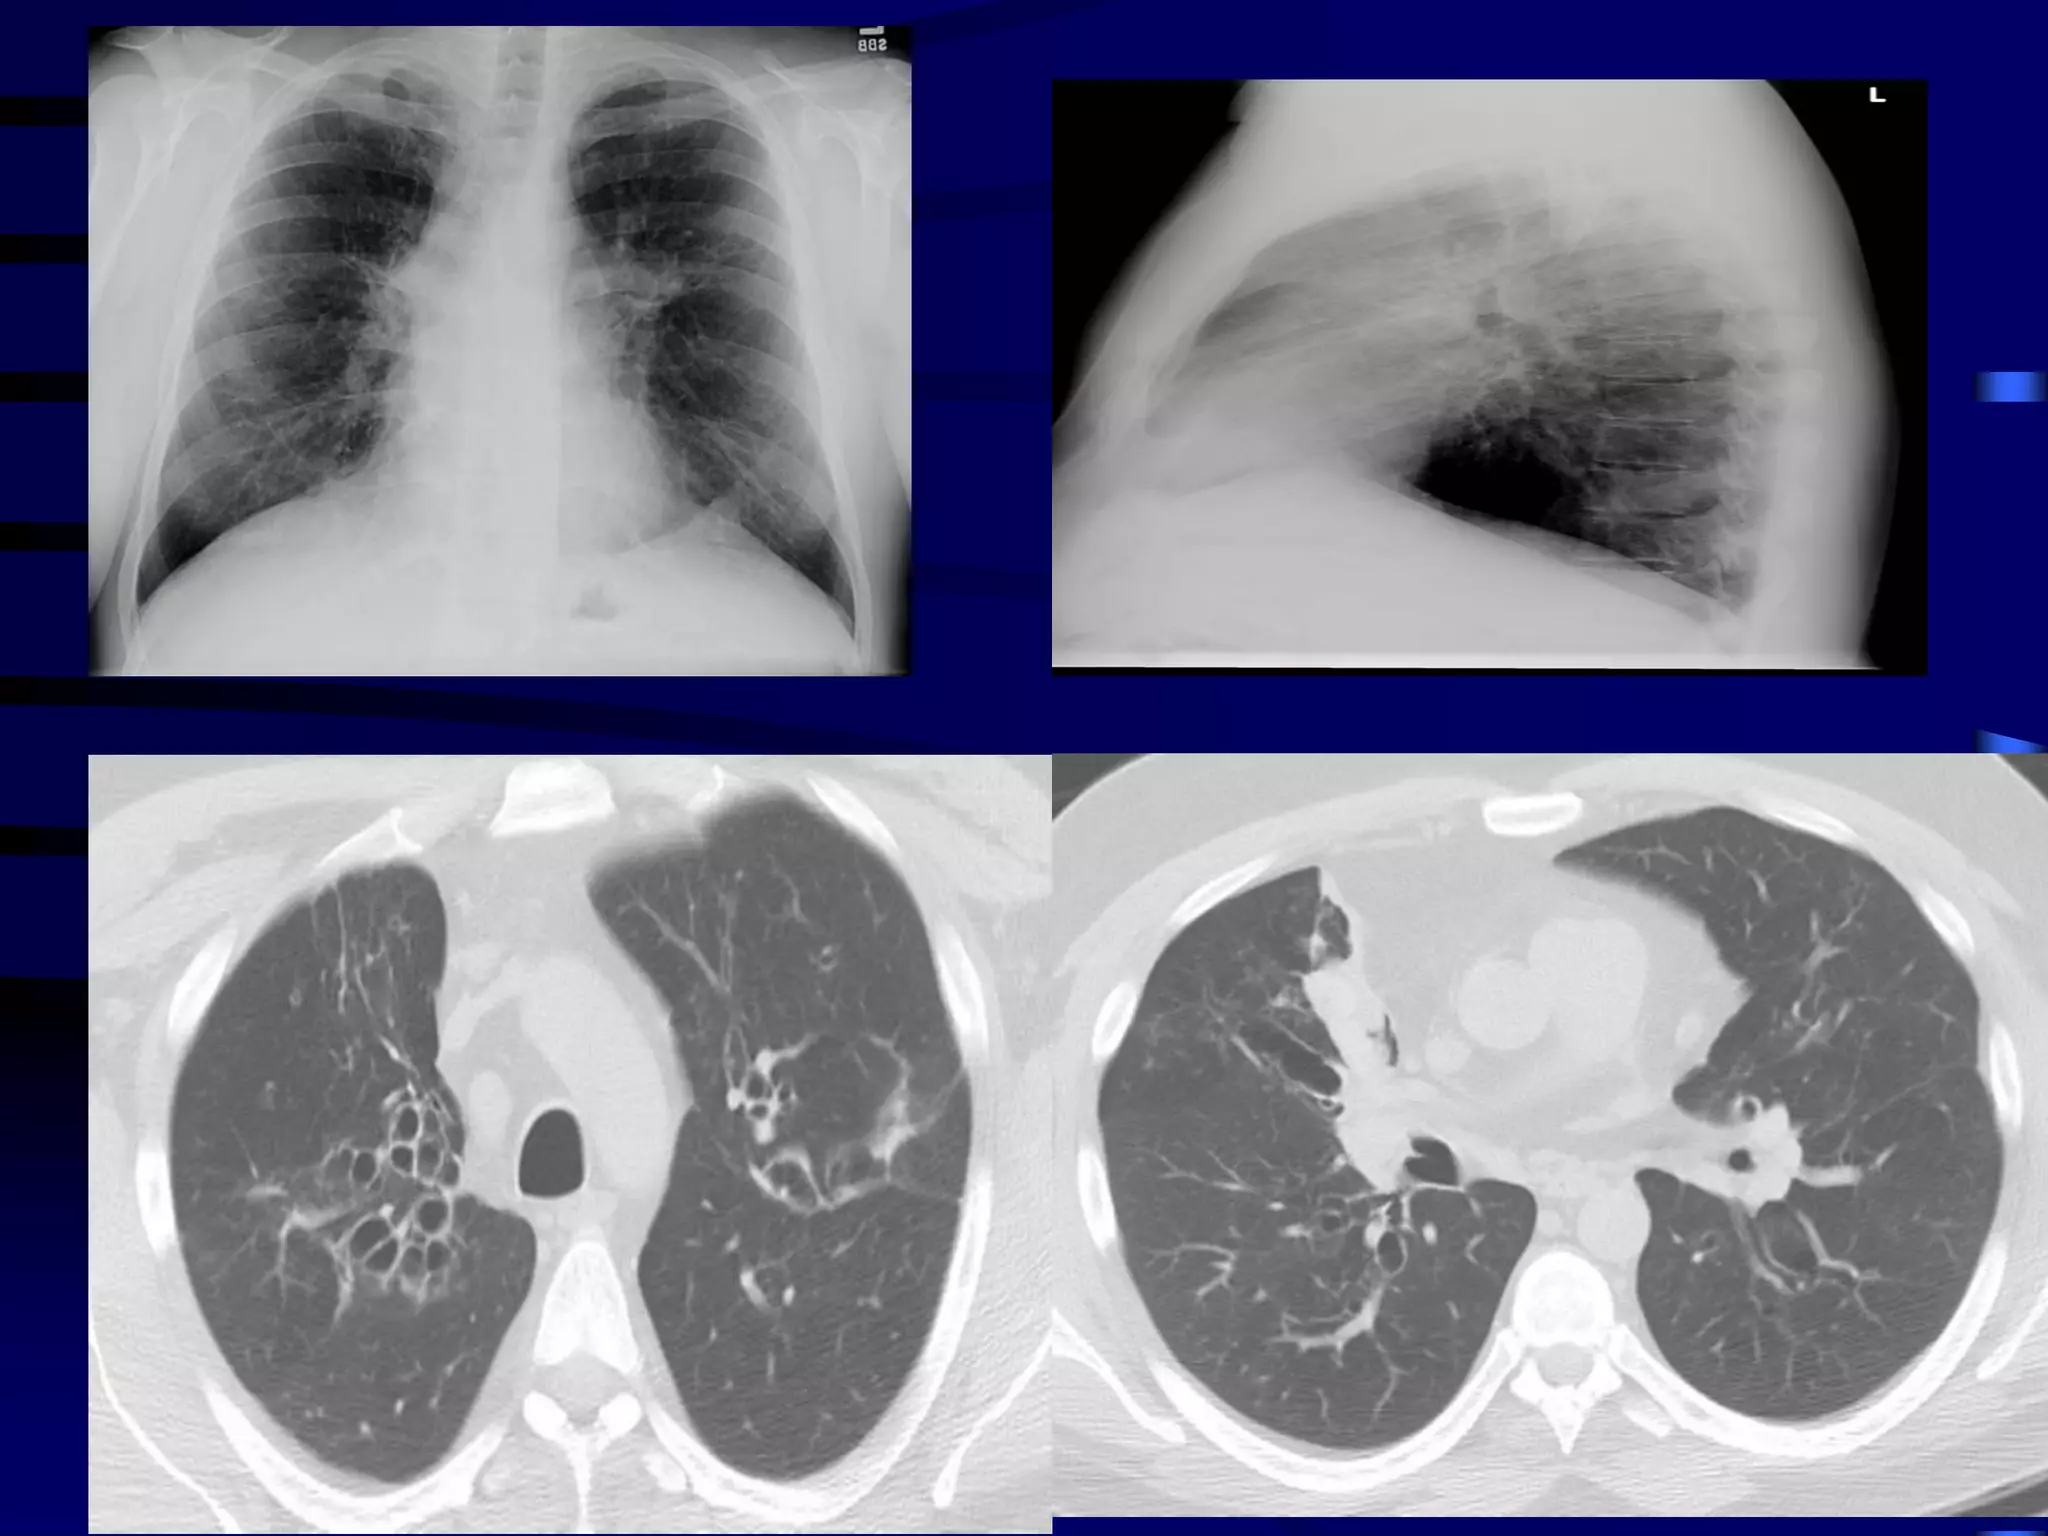

A 46 year old man comes to your clinic for management of

his asthma. He takes high-dose inhaled corticosteroids

and a long-acting beta agonist, along with a leukotriene

inhibitor. His adherence and technique are perfect.

He still has symptoms of cough, wheezing, and chest

tightness that bother him most days and nights each

week. He is using albuterol daily. The symptoms persist

when he goes on vacation out of state.

Sputum culture is negative. IgE level is 3,600 ng/mL. His

primary doctor obtained imaging and a chest CT, which

are shown.

Case 3

Allergic bronchopulmonary aspergillosis (ABPA) is an

ongoing hypersensitivity reaction in response to

bronchial colonization by Aspergillus, and is a common

cause of poorly controlled asthma. Cystic fibrosis

patients are also often affected. Bronchial obstruction

by mucus and chronic inflammation can lead to

bronchiectasis and lung fibrosis with irreversible loss

of lung function.

Clinical features: Cough productive of sputum, frequent

"bronchitis"; often with dyspnea and wheezing.

Diagnosis:

By constellation of symptoms and objective

findings. "Classic" ABPA would include the

following:

Asthma history

Immediate reactivity on skin prick with Aspergillus

antigens

Precipitating serum antibodies to A. fumigatus

Serum total IgE concentration >1,000 ng/mL

Peripheral blood eosinophilia >500/mm3

Lung opacities on chest x-ray or chest HRCT

Central bronchiectasis present on chest CT

Elevated specific serum IgE and IgG to A.

fumigatus

A skin test is the best first test, as it

is considered 100% sensitive (i.e., a

negative test rules out the condition).

A serum IgE < 1,000 or negative

precipitating antibodies also rule out

ABPA with high confidence.